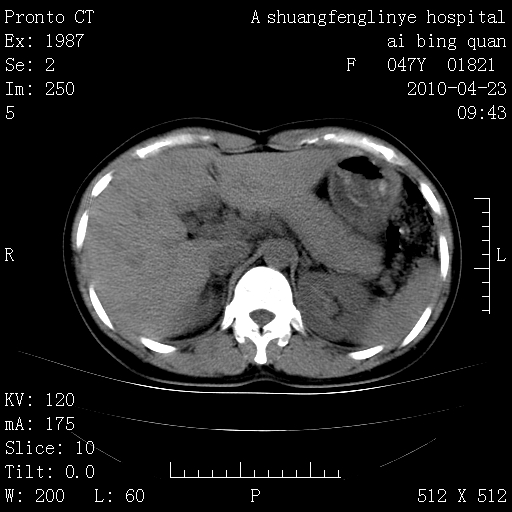

标题: CT25944:胸痛、气短、前几日高烧!肺Ca?请会诊! [打印本页]

标题: CT25944:胸痛、气短、前几日高烧!肺Ca?请会诊!

kaolv 周围型肺癌并同肺转移

双肺多发结节,考虑转移瘤,肺癌肺转移不除外

周围型肺癌并肺转移

双肺多发结节,部分密度较高,最大结节边缘光滑。临床有“胸痛、气短、前几日高烧”病史。首选考虑:右肺感染性病变!建议积极消炎后复查!

建议抗炎治疗后复查,排除肿瘤性病变。